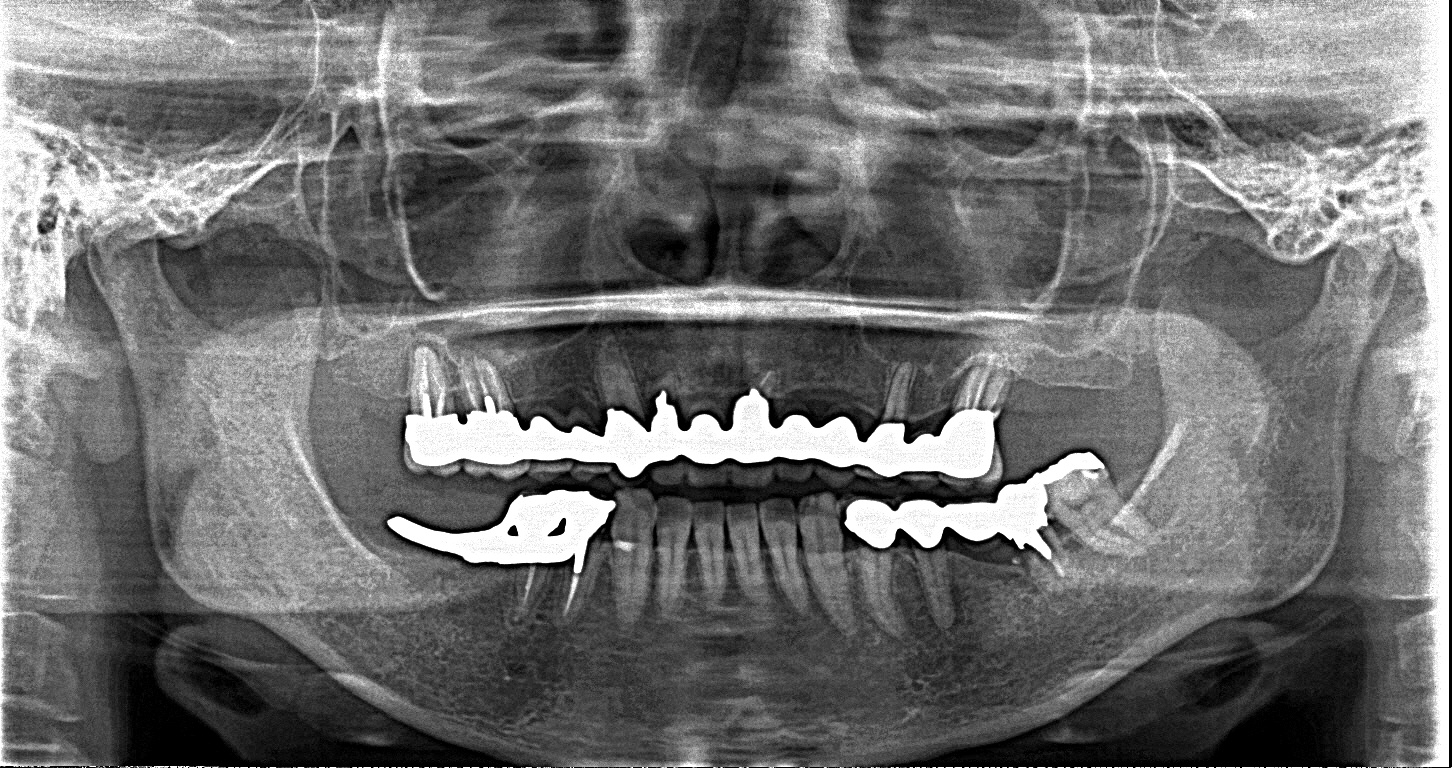

■術前パノラマ